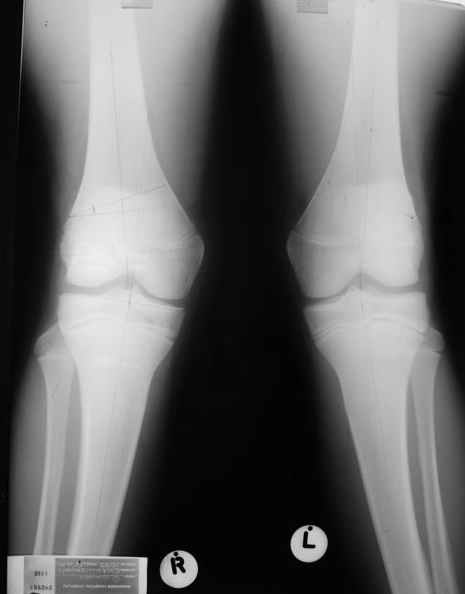

Уважаемый Евгений ! Спасибо за ответ, но мне представляется, что в нашем случае основной проблемой является не столько прогрессирующий вальгус конечности, сколько несросшийся перелом мыщелка бедра и дефект мыщелка большеберцой кости - вероятно первичная репозиция выполнялась без пластики.

Относительно "рубцовой подушки" я имел в виду остатки мениска ( частично вколоченного в дефект мыщелка и фрагменты хряща), все таки на рентгенограммах суставная щель в этом отделе чем то заполнена. Что касается некроза мыщелка бедра, то мне кажется он уже наступил - томограмма ноябрь5.

С учетом всего сказанного - наличия прогессирующего вальгуса конечности, довольно приличного объема движений, имеющегося, вероятно, некроза мыщелка бедра, наиболее рациональным представляется удалить пластину с б\б кости, произвести остеотомию б\б кости с коррекцией вальгуса, разгрузив тем самым наружный отдел сустава, и синтезировать фрагменты голени накостным фиксатором. Максимально тано начать восстановление движений в суставе. Скорее всего рано или поздно речь о протезировании всеже возникнет, но мы хотя бы будем иметь приличную ось конечности.

С *вколоченным* мениском встречаться не приходилось, нередко при импрессионных переломах наблюдал центральную дислокацию мениска по типу bucket handle, что в этой ситуации может объяснить сгибание сустава до 90 и разгибание 160 градусов, отчасти невозможность полностью разогнуть ногу при Рг графии сустава затрудняет интерпретацию прямой проекции сустава.

Сканирование с Тс99 поможет верифицировать наличие некроза мыщелка бедра, если использовались титановые винты, то магнитно-резонансное исследование будет более информативным. При подтверждении некроза, бедренная или всокая тибиальная остеотомии, очевидно, будут малоуспешны, поэтому альтернатив артропластике похоже не останется. Наблюдений реваскуляризации мыщелка бедра после туннелизации у меня нет, надо покопаться в литературе.

А какая сейчас амплитуда движений в коленном суставе?

Вообще, про какие восстановительные операции не думается, все равно в сторону эндопротезирования мысль сворачивает... Тотальное, однокомпартментное ли, это гуру виднее.

Сгибание до 90гр., разгибание да 160гр.